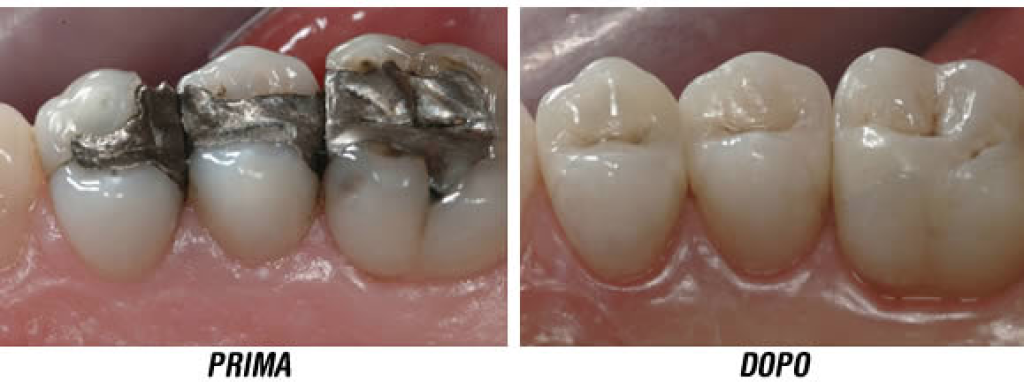

Sostituzione di vecchie otturazioni

Nel tempo, le otturazioni si possono usurare, crepare o staccare parzialmente, lasciando spazio a infiltrazioni batteriche. In questi casi è opportuno rimuoverle e rifarle per evitare nuove carie secondarie.

Cementi vetroionomerici (utili nei bambini o zone non estetiche)

Resina composita (estetica, colore simile al dente)

Amalgama (oggi meno usata, più visibile). Negli ultimi anni, l’amalgama dentale è stata progressivamente sostituita da materiali più moderni principalmente per tre motivi. Innanzitutto contiene mercurio, che pur essendo stabile una volta indurito, ha sollevato dubbi sul suo impatto a lungo termine sulla salute e sull’ambiente. In secondo luogo, l’amalgama ha un colore metallico grigio, poco estetico, che risulta molto visibile soprattutto nei denti anteriori o quando si sorride. Infine, questo materiale richiede una preparazione più invasiva del dente, comportando la rimozione di più tessuto sano per garantire la ritenzione meccanica. Al contrario, le moderne resine composite sono biocompatibili, mimetiche (del colore del dente) e permettono tecniche più conservative, preservando al massimo la struttura dentale naturale.